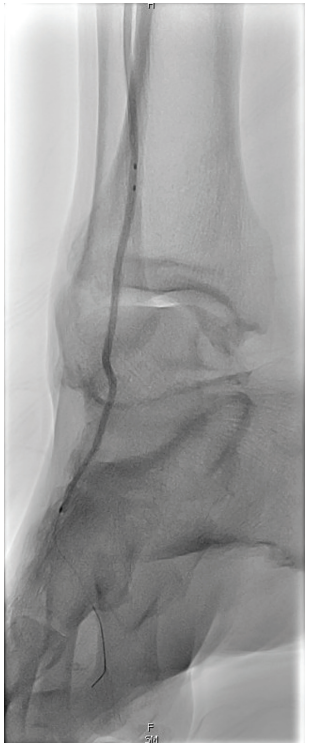

Figure 7. Pedal arch branch vessel

angioplasty to improve microcirculation.

• Pedal arch branch vessel angioplasty to improve microcirculation (Figure 7).